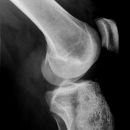

Kniegelenk